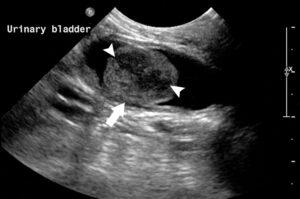

Bladder scan is to identify urinary bladder stones (dense white mass in centre of screen).

Bladder Ultrasound showing a tumour